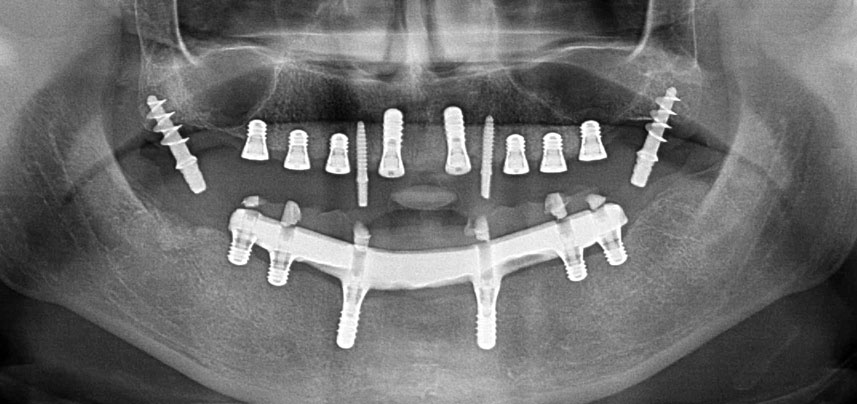

Implantatgetragene festsitzende Prothesen verbessern bei zahnlosen Patienten Kaufunktion und Lebensqualität. Infolge von Knochenresorption und umfassender Pneumatisation der Nebenhöhlen verfügte eine Patientin nur über eine minimale Knochenhöhe im Seitenzahnbereich des Oberkiefers. Die Implantatlager wurden mit einem piezochirurgischen Gerät und einem neuen Set spezieller Instrumente präpariert. Es wurden zwei 10-mm und sechs 4-mm-Implantate inseriert, die zur Abstützung einer steggetragenen und verschraubten CAD/CAM-Versorgung dienten.

Drei Jahre später war es Zeit für eine gleichartige Oberkieferprothese. Basierend auf der DVT-Planung wurde durch Verwendung kurzer Implantate eine Sinusaugmentation vermieden und die geplanten Implantatpositionen wurden mit einer Bohrschablone auf den Kieferkamm übertragen (Abb. 1 und 2).

Wegen des relativ harten Knochens (D2) an den Positionen 11 und 21 wurden die 10 mm langen Implantatlager in diesem Bereich abschließend mit einem 4-mm-Spiralbohrer, dem chirurgischen Winkelstück WS-75 L von W&H und dem W&H Implantmed Implantologiemotor in Verbindung mit dem optionalen W&H Osstell ISQ module präpariert. Im Gegensatz dazu wurde der weiche Knochen der Implantatlager im Seitenzahnbereich mit dem Piezomed I3P auf den abschließenden Durchmesser von 3 mm erweitert. Die Implantate wurden dann transgingival eingesetzt, die Einheildauer betrug drei Monate (Abb. 6-10). Die vorhandene Prothese wurde auf vier provisorischen Implantaten abgestützt (Abb. 8).